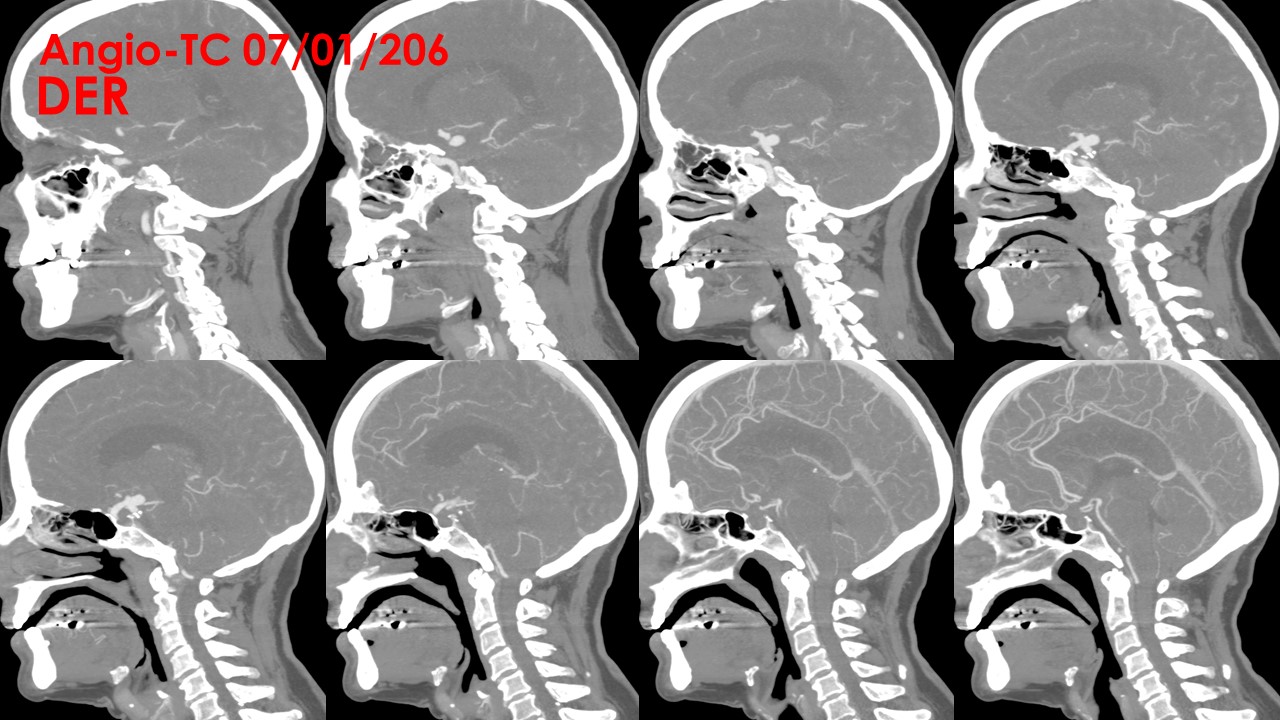

ANGIO TC:

Troncos supraorticos permeables, sin variantes anatómicas reseñables.

Origen fetal de ambas arterias cerebrales posteriores.

A nivel de la arteria carótida supraclinoidea derecha, entre la salida del ACoP (ACP) ipsilateral y la ACA derecha se observa una imagen de adición opacificada de aspecto nodular, de aproximadamente 11 mm x 8 mm, compatible con aneurisma, probablemente responsable de la hemorragia actual. A nivel de la arteria carótida supraclinoidea izquierda se observa otra imagen de características similares de 7 mm x 4.5 mm, compatible con aneurisma de dicha arteria.

No se visualizan otras dilataciones aneurismáticas a nivel intracraneal.

No se observan estenosis valorables en sistema arterial intra ni extracraneal.